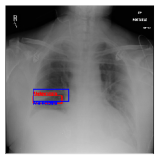

By using the training result of the Adaptive DBN, the heatmap images were generated in addition to detection of B-Box. The heatmaps in Fig. 10 to Fig. 14 show the detection result of B-Box and the generated heatmap for some images. The red and blue rectangles in the image are given B-Box and detected B-Box, respectively. A heatmap is represented by the continuous value of range , where the color map is jet color array (red means high value, while blue means small value). The diseases for detected B-Boxes in Fig. 10 to Fig. 14 were as follows; Infiltration (Fig. 10), Mass (Fig. 10), Nodule (Fig. 10), Mass and Pneumothorax (Fig. 10), Atelectasis (Fig. 14), Infiltration (Fig. 14), Atelectasis (Fig. 14), Atelectasis (Fig. 14).

Overall, the red area of the generated heatmap included in both the given B-Box and detected B-Box. On the other hand, the blue or yellow areas didn’t include in these B-Boxes. This tendency was seen in not only large diseases (e.g. Cardiomegaly or Infiltration) such as Fig. 10, but also small diseases (e.g. Mass or Nodule) such as Fig. 10. We consider that the experimental results caused by the discrete heatmap with binary output of final RBM layer instead of continuous heatmap. As a result, the red regions represents localization with strong relation to diseases and blue regions represents localization with weak relation. The generated heatmap shows the portion with strong relation more clearly.

In Fig. 14, the detected B-Box was located at a little upper than the given B-Box. The red area of the heatmap was also at upper position. The detected B-Box is slightly larger than the given B-Box. The detected B-Boxes are almost same as the given B-Boxes except the different size. For better detection capability, the feature of the generated heatmap will be investigated with the medical specialists.